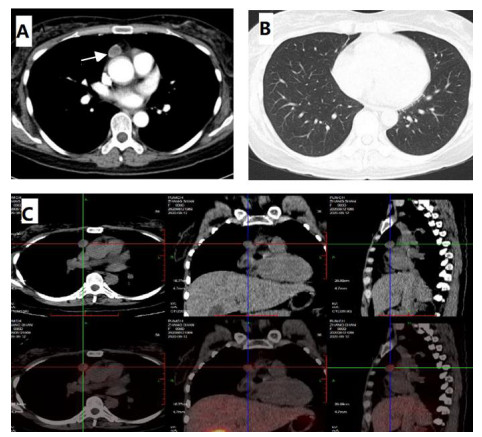

第一次收住院诊疗经过:完善常规生化提示低钾血症、高脂血症,超声心动图:微量心包积液,EF67%。肺通气功能正常。库欣综合征定性定位诊断方面,血总皮质醇(血F)(8AM) 69.6 μg/dL, ACTH(8AM) 664.0 pg/mL, 24 h尿游离皮质醇(24HUFC)2 723.2 μg/24 h,大剂量地塞米松抑制试验(见表 1); 标筛查:AFP 4.6 ng/mL, CA19-9 22.2 U/mL, CEA 3.0 ng/mL, CA125 38.4 U/mL, 细胞角蛋白19片段Cyfra211 6.0 ng/mL, CA242 19.0 U/mL, CA72-4 8.6 U/mL, CA15-3 12.9 U/mL, ProGRP 26.0 pg/mL, NSE 15.4 ng/mL。生长抑素受体显像:前纵隔结节,生长抑素受体高表达灶,考虑神经内分泌肿瘤可能性大;双侧肾上腺增生。(图 1C);垂体平扫+动态增强MRI:垂体后叶短T1信号存在垂体左翼强化减低区,考虑微腺瘤。胸增强CT:前纵隔占位,结合病史,不除外异位ACTH瘤(图 1A);TB细胞亚群11项: %memory T4 78.1%, B% 17.9%, T4% 17.6%, T8% 42.1%, RAT4% 21.9%, NaT4% 21.7%, 28T8% 32.1%, DRT 8% 76.2%, 38T8% 83.0%, T4/T8 0.42%, 垂体前叶功能,甲功1:TSH 0.077 μIU/mL, FT4 1.73 ng/dl, FT3 2.17 pg/mL, GH < 0.05 ng/mL, IGF1 132 ng/mL。FSH 2.13 IU/L, LH 0.26 IU/L, E2(Ⅱ) < 15 pg/mL, T 1.96 ng/mL, PRL 6.9 ng/mL, P 5.31 ng/mL。MEN筛查,GASTRIN 260 pg/m,ProGRP 23.9 pg/mL。降钙素(CT) < 1.5 pg/mL,钙素原PCT 0.23 ng/mL, CK 33 U/L。IPSS+DDAVP兴奋试验示基线时中枢和外周ACTH无梯度(见表 2),结合大剂量地塞米松抑制实验不被抑制,支持异位ACTH综合征,考虑胸腺占位为责任病灶可能。治疗方面,入院后予口服及静脉补钾、螺内酯纠正低钾血症,监测血糖,餐后2 h血糖高,给予胰岛素及口服降糖药后血糖基本达标。患者前纵隔结节考虑为异位ACTH瘤可能大,2020-08-26行VATS胸腺及肿瘤切除术,术后恢复良好,激素替代方案由围术期静脉应用琥珀酸氢化可的松逐渐过渡为醋酸氢化可的松片早40 mg,晚20 mg替代治疗后出院(图 3主要指标趋势及用药情况)。2020-08-31无明显诱因出现发热,体温最高达39℃,当地诊所静点“头孢类抗生素”、口服布洛芬治疗2 d,仍间断发热,并出现站立后头晕,当时血压76/40 mmHg,就诊当地医院,查血常规:WBC 6.01×109/L, NEUT% 85.2%, LYM% 13%; CRP 194.74 mg/L; CMV DNA阳性;胸部CT提示双肺弥漫渗出,考虑“重症肺炎I型呼吸衰竭”于当地重症监护室予以“无创呼吸机辅助呼吸,哌拉西林他唑巴坦、奥司他韦、伏立康唑抗感染,丙种球蛋白免疫支持”。治疗效果欠佳,胸闷、憋气逐渐加重,伴咳少许白色黏痰。2020-09-03就诊本院,考虑重症肺炎收入急诊重症监护病房,第2次收住院诊疗经过:呼吸方面:复查胸CT提示:双肺弥漫炎性改变,双侧胸腔积液并左下肺轻度膨胀不全(图 2A 、B)。予高流量氧疗支持,完善肺泡灌洗液: PCP DNA阳性(+),CMV(+),结合病史、症状、体征及辅助检查证据,考虑肺孢子菌肺炎、巨细胞病毒肺炎、混合细菌感染,头孢他啶1 g/8 h、莫西沙星0.4 g/d、TMP/SMX 3片3次/d,更昔洛韦0.25 g/8 h,呼吸困难逐渐改善,复查CT病灶明显吸收(图 2C 、D)。内分泌方面:考虑EA导致CS术后,激素替代治疗中合并机会性感染,调整治疗:停用口服,给予琥珀酸氢化可的松50 mg/6 h。口服降糖药控制类固醇糖尿病,口服碳酸钙片治疗骨质疏松。原发病方面:结合病理胸腺病灶考虑内分泌来源类癌,恶性程度低,无需放化疗。2020-09-30出院时患者无发热、头晕、纳差、恶心、呕吐、电解质紊乱、低血糖等肾上腺皮质功能不全表现,氢化可的松早40 mg-午20 mg逐渐减量(图 3主要指标趋势及用药情况),激素替代期间TMP/SMX 2片/d预防感染,门诊随诊。

| A:纵隔窗白色箭头提示前纵隔占位1.8×1.6cm;B:肺窗未提示感染感染;C:99mTc-HTOC:前纵隔结节,生长抑素受体高表达灶 图 1 8-13胸部增强CT |

2.2 本例患者的诊疗要点有哪些?定位定性诊断:患者首次入院既表现为高皮质醇血症的体貌(包括脸圆、痤疮、锁骨上脂肪垫、唇上小须等),同时伴有双下肢浮肿及持续的中-重度低钾血症。结合辅助检查特点血皮质醇水平、24 h游离尿皮质醇升高,血皮质醇节律消失,小剂量地塞米松试验未被抑制,考虑库欣综合征定性诊断明确。定位诊断方面,患者外院和本院查血尿皮质醇显著升高的同时ACTH不被抑制,符合ACTH依赖的CS,结合大剂量地塞米松抑制试验未被抑制,垂体动态增强核磁未见明显异常,奥曲肽显像、99mTc-HTOC等影像学均提示前纵隔结节生长抑素高摄取,考虑异位ACTH综合征明确,犯罪病灶在前纵隔,本病常见于异位肿瘤分泌促肾上腺皮质激素,如肺癌、胸腺瘤、支气管类癌、消化道和卵巢肿瘤等,通常病情进展快,ACTH升高明显,往往存在严重低血钾、代谢性碱中毒等。